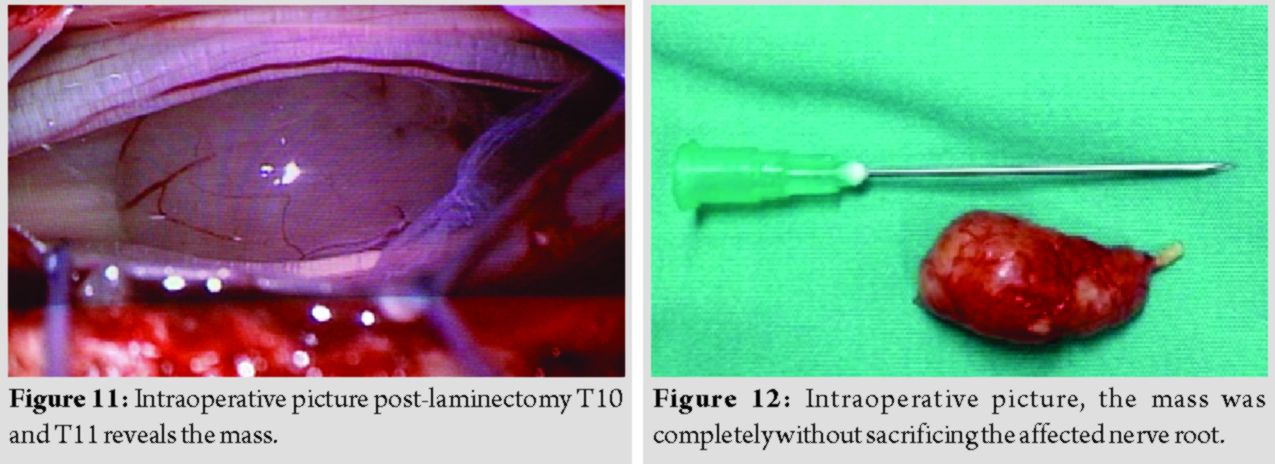

A 53-year-old lady presented with complaint of back pain and bilateral lower limb weakness for a year duration, associated with urinary incontinence for 2 months duration. Examination reveals normal tone, power over the right lower limb was more affected (MRC Grade 2) as compared to the left lower limb (MRC Grade 3), lower limb reflexes were brisk, and sensation was reduced from T11 dermatome onward. Magnetic resonance imaging reveals a well-defined intradural extramedullary mass at T11, compressing on the conus medullaris (Fig. 9 and 10).

She underwent laminectomy of T10 and T11 with microscopic assisted excision of the tumor. The mass was successfully removed completely without sacrificing the involved nerve root (Fig. 11 and 12).

Her neurological recovery was remarkable despite being symptomatic for a year duration. By post-operative day 2, she claims that her back pain has completely resolved. She regained bladder control at 1-week post-operative and was ambulating with aid. At 2 weeks post-operative, she was able to ambulate without aid. Final diagnosis was confirmed through histopathology. None of these patient suffered from neurofibromatosis. No instrumentation was done to stabilize the spine as only a single-level laminectomy was involved. The surgeon took careful measures to ensure the facet remains untouched and thereby maintaining the stability of the spine. These patients have followed up for the past 7 years with no progressive kyphosis noted or clinical symptoms and signs suggesting recurrence.